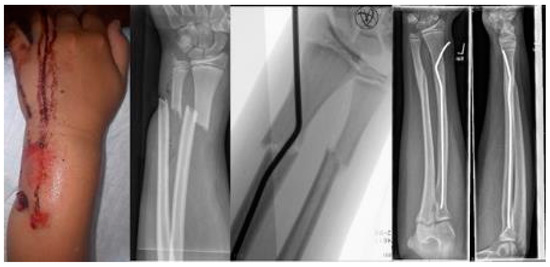

The youngest patient was a two-year old boy, who presented with an unacceptable secondary displacement two weeks after trauma and, thus, this fracture became a rare indication for osteosynthesis in this age group (Scheme 2). The eldest was 17 years of age and did not show epiphyseal plates anymore (Scheme 3). This patient, however, suffered a new trauma 3 weeks later and underwent a redo-procedure in another hospital and, thus, was lost to follow-up. We even treated an open forearm fracture (on the ulnar side) with this technique (Scheme 4), leaving the fracture of the ulna to spontaneous healing and correction. This was because the risk of osteomyelitis due to intramedullary nailing of the open ulnar fracture to achieve a “nice X-ray” was estimated to be much higher than the risk of a remaining misalignment. Even a redo-procedure of a fracture that we had seen for the first time 4 weeks after an unacceptable K-wire osteosynthesis was successful, this time using a modification of the technique with a bend, rather than a kink distal to the fracture. Please note that the pre-bent nail pushed the 4-week-old fracture into a correct position without open reduction (Scheme 4). Last but not least, curiously, we saw one patient who suffered identical fractures in both arms, so we could perform the procedure twice in one operation (Scheme 5).

Scheme 1. Closed reduction 4 weeks after insufficient k-wire osteosynthesis with a bend instead of the distal kink as a variant of this procedure.

Scheme 4. Open forearm fracture leaving the fracture of the ulna to spontaneous correction.